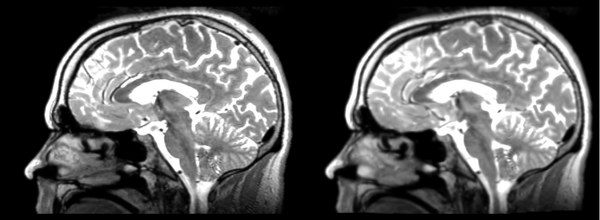

Rigid

- 53-t2 -> 31-t1 = rig1

- rig1 -> 53-t2 = rig2

Significant blurring, but every feature is in it's proper place.

Deformable B-spline

- 53-t2 -> 31-t1 = Bspline1

- Bspline1 -> 53-t2 = Bspline2

Superior frontal enlargement, odd upward shifting in rear of brain, distortions everywhere.